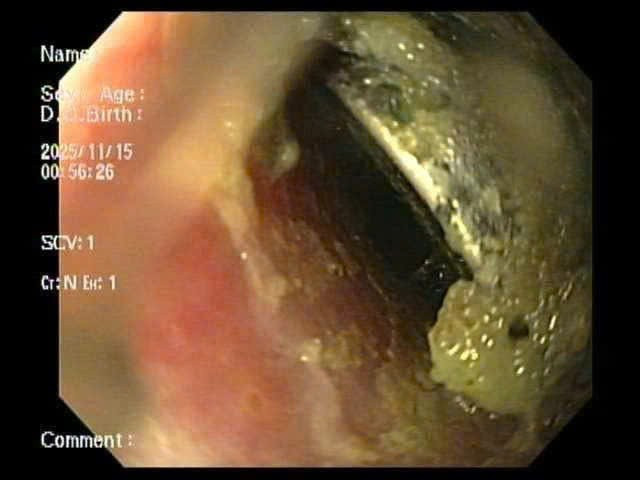

Kết quả X-quang cho thấy dị vật mắc lại ở thực quản. Các bác sĩ tiến hành nội soi cấp cứu và gắp thành công viên pin. Tuy nhiên, quan sát trực tiếp tại vị trí mắc cho thấy vùng thực quản đã bị ăn mòn và loét lớn - minh chứng pin cúc áo có thể gây tổn thương nặng nề chỉ trong thời gian rất ngắn, dù trẻ được đưa đến viện sớm.

Hình ảnh dị vật là pin cúc áo trong thực quản trẻ. Ảnh: Bệnh viện Nhi Hải Phòng